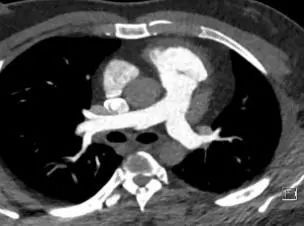

肺CTA:双肺支气管血管束增多。右肺中叶内段及左肺上叶下舌段见少许索条影。前上纵隔胸腺密度不均,考虑胸腺退化不全。心外形增大。肺动脉主干、左右肺动脉干及各叶、段、亚段肺动脉形态走行未见异常,管腔显影良好,未见确切充盈缺损病灶。(影像学资料见下图)